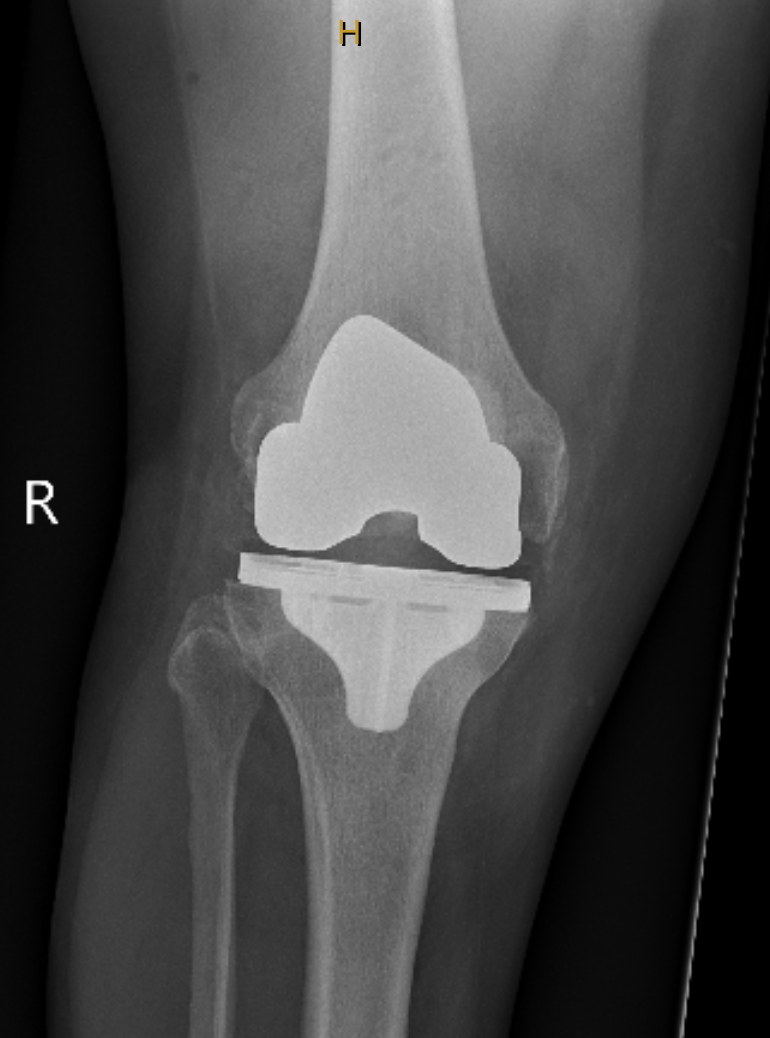

Knee Replacement

A knee replacement removes the worn cartilage and damaged joint surfaces of the knee and replaces them with smooth, durable artificial components. The new metal and plastic surfaces are designed to glide comfortably and restore stable movement.

It is considered when pain, stiffness, or loss of function from arthritis or certain knee injuries affects daily activities and non-surgical treatments are no longer providing relief.

The aims are to reduce pain, improve walking and knee function, and restore day-to-day comfort.

Modern knee implants provide reliable long-term performance. About 90 to 95 percent function well at 15 years, with durability affected by age, activity levels, and overall health.